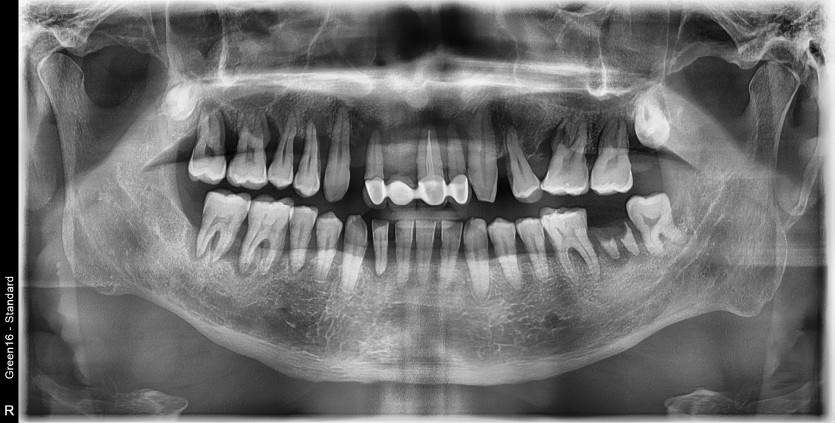

상악 전체 임플란트 증례입니다.(하악 일부)

14개의 임플란트로 완성하였습니다.